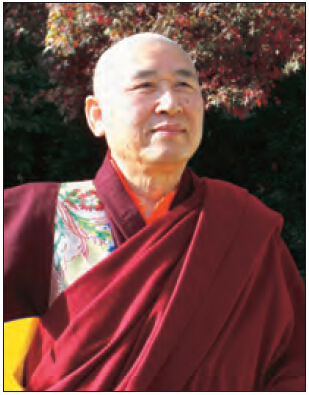

开初仁波且MRI核磁共振脑断层扫描医学图片

这是开初仁波且修金刚换体禅后,在加州医疗中心检查身体时拍摄的MRI核磁共振检测照片。可以清晰看见开顶后,头顶大乐轮门处头骨、皮肉等大开,开口宽约两英寸,脑髓开出鸡蛋大的凹洞。更令人震撼的是,当开初仁波且拍摄扫描照片时,整块头骨突然不见,而呈现出弥勒菩萨乳胎婴童像,身搭俱袍,手脚呈现,心空大洞,跏趺而坐,在电脑上清晰可见五官面容,眼睛、鼻子、嘴巴。